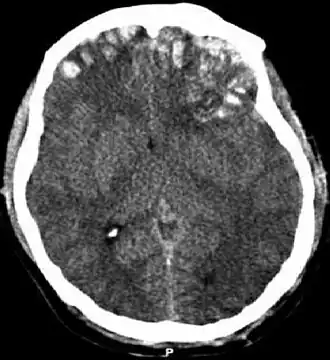

| Tomografia computadorizada mostrando contusões cerebrais, hemorragia nos hemisférios, hematoma subdural à esquerda e fraturas do crânio. | |